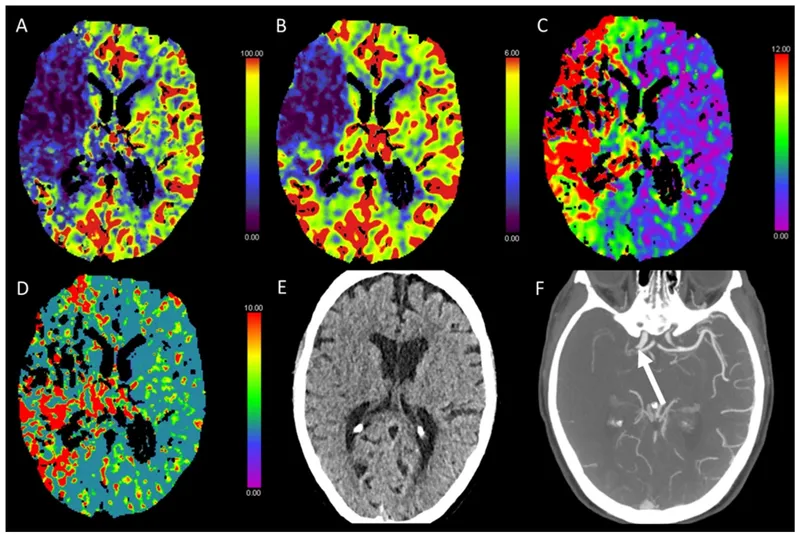

Dementia Imaging (FDG-PET): Assesses regional cerebral glucose metabolism. Characteristic patterns aid diagnosis.

Dementia Type FDG-PET Hypometabolism Pattern Alzheimer's Disease (AD) Bilateral temporoparietal, posterior cingulate, precuneus (📌 PTP: Parieto-Temporal, Posterior cingulate) Frontotemporal Dem. (FTD) Predominantly frontal and/or anterior temporal lobes Lewy Body Dementia (LBD) Occipital hypometabolism (sparing of mid/posterior cingulate: "cingulate island sign") Vascular Dementia (VaD) Multiple, asymmetric cortical and/or subcortical areas, often patchy

Epilepsy Imaging: Localizes epileptogenic foci.

- Ictal SPECT ($^{99m}$Tc-HMPAO or $^{99m}$Tc-ECD): Shows ↑ perfusion at seizure onset site.

⭐ Ictal SPECT is more sensitive than interictal SPECT for localizing epileptogenic foci and requires rapid tracer injection (ideally within 30-60 seconds) during or immediately after seizure onset.

- Interictal PET (FDG): Reveals ↓ metabolism in the epileptogenic zone.

- Interictal SPECT: Often normal or may show ↓ perfusion in the epileptogenic zone during the interictal phase.